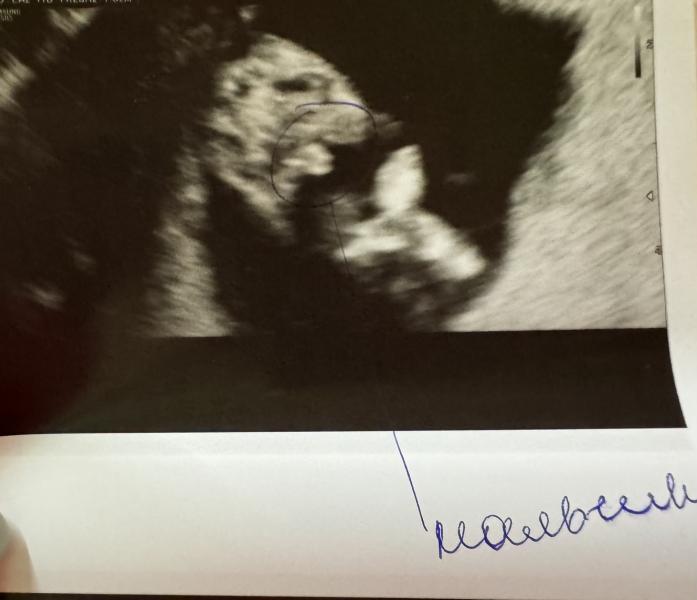

У девочек так не торчит 😏

Мальчишка и сразу видно причиндал 🙌🏻

Ну вот вроде похоже на девочку, но теперь я понимаю что можем ошибаться 😄

Я тоже больше пирожок вижу)))

У вас половой бугорок на девочку похож на самом деле )

А вот вторая фотка там вид снизу) сказали прям видно, что мальчик 🥰 обвели ручкой даже причиндалы 🙈

Как чудесно ♥️ не стал скрывать малыш. Все сразу показал 🤭

У меня так же сразу все показал как у вас на фото 😁обычно девочки прячут